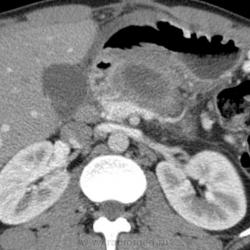

Мужчине 25 лет, сильно алкогольный анамнез. Позади 2 операции по дренированию псевдокист поджелудочной железы, перед очередной операций область затребовала КТ по месту жительства. Сначала нативное (бесконтрастное исследование).

Есть кровоизлияние в псевдокисту (в теле). Явно псевдоаневризм не видно (конечно для жтого надо вмально перекрутиьт исследование на рабочейстанции).

Есть выраженная регионарная портальная гипертензия, форимрование параспленальных и пеоригастральных венозных коллатералей - за счет того что произошло сужение селезеночной вены.

Хотя и напрашивалась)). Коллатерали я впервые такие увидела. Киста сдавливает селезеночную артерию и вену.

А в подпечёночном пространстве что, кпереди от кисты тела поджелудочной? И можно ли "мелочевку" в 7-м сегменте назвать гемангиомой (на нативе она изоденсна)?